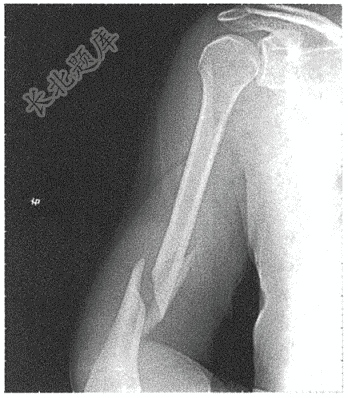

- 简答题患者男性,28岁,摔伤5小时入院。查影像学检查如下: